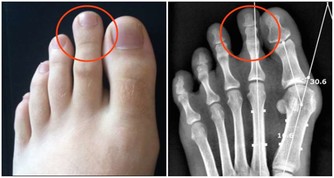

9、防止結石

結石的形成主要是體內的磷酸鎂等無機鹽類在體內結晶沉積形成。而出汗能有效排出體內鹽分並保留骨骼中的鈣質。這一生理過程能限製鹽和鈣在腎臟和尿液中堆積起來,而這正是結石的來源。出汗較多的人會喝更多的水,從而也防止了結石的形成。